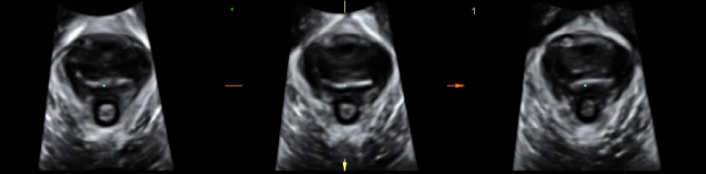

王阿姨的检查结果

(缩肛状态盆膈裂孔三维成像)